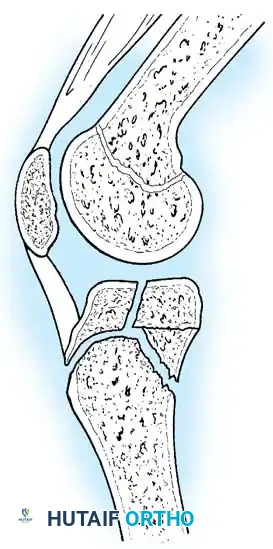

- Type IV Fractures: These cross both the epiphysis and metaphysis. They carry a high risk of growth arrest and joint incongruity. Stress radiographs are invaluable for diagnosing associated ligamentous instability, which may masquerade as a simple non-displaced physeal fracture.

Fig. 33-176: Physeal fracture with major ligamentous injury. A, Nondisplaced Salter-Harris type IV fracture. B, Stress radiograph shows fracture displacement and medial joint line opening, implying tibial collateral ligament injury. C, Intraoperative view during ORIF.

Triplane Variants: Variants of Salter-Harris III and IV fractures have been described as "triplane fractures of the proximal tibial epiphysis," analogous to the more common distal tibial triplane fractures. These occur during the transitional phase of physeal closure. If displaced, they require precise ORIF.

Fig. 33-177: Sagittal view of the knee depicting a coronal split fracture of the proximal tibia epiphysis through a partially closed physis.

Advanced imaging (CT with sagittal and coronal reconstructions, or MRI) is critical to determine the exact fracture geometry and the degree of articular step-off. Plain radiographs often underestimate the severity of the displacement, providing a false sense of security.